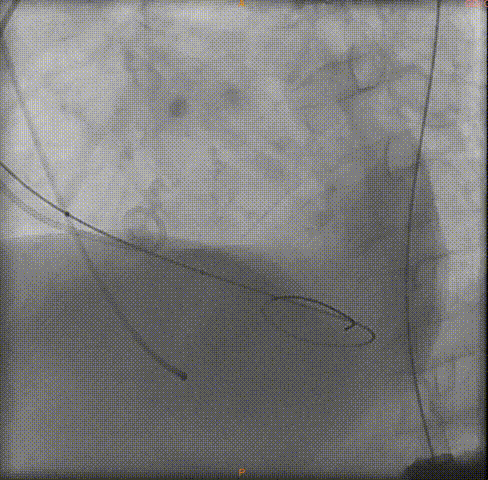

导丝跨瓣

球囊预扩

瓣膜定位